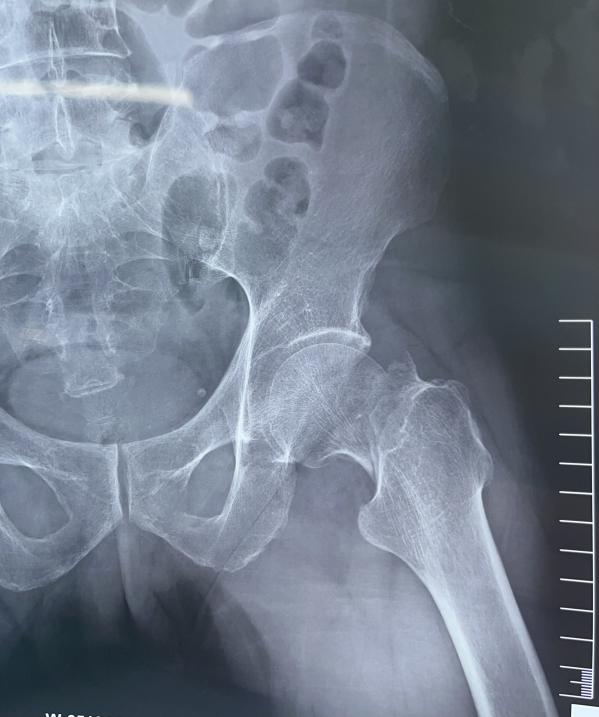

术中术后透视